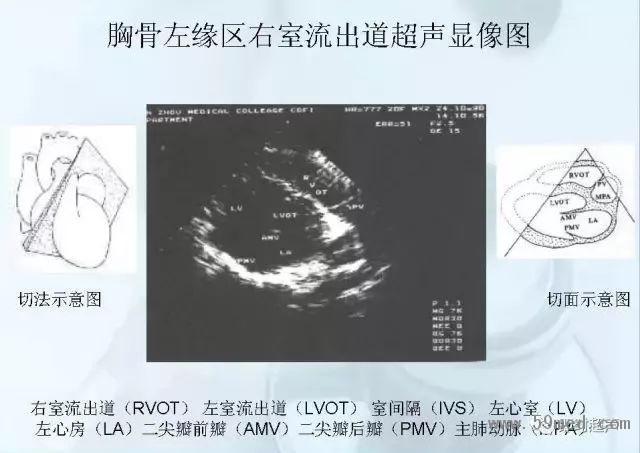

![]() ![]() ![]() ![]() ![]() ![]() ![]() ![]() ![]() ![]() ![]() ![]() ![]() ![]() ![]() ![]() ![]() ![]() ![]() ![]() ![]() ![]() ![]() ![]() ![]() ![]() ![]() ![]() ![]() ![]() ![]() ![]() ![]() ![]() ![]() ![]() ![]() 【注:本文來源于即時超聲,版權(quán)歸原作者所有,如有侵權(quán) 請聯(lián)系 速刪】 =========================== 【閱精彩*悅分享】隨手點擊轉(zhuǎn)至朋友圈,與大家一起分享精彩資訊!當(dāng)然您也可以通過以下方式找到我,與您共同分享藍(lán)韻影像超聲的更多精彩!微信號:landultrasound 電話:+86-0755-66869896 24小時客服熱線:400-888-6452